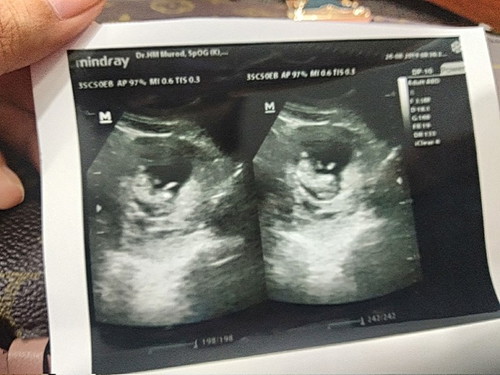

hasil usg

Hai bunda2 saya meme salam kenal yaa, sy bru sj pregnant kali pertama jd masih awam skli utk ilmu sputar maternitas hehe.. Mnrut hsil usg dokter usia janin mnunjukkan 8weeks sdgkn mnrut app usianya udah 11weeks.. Agak bingung dong antara hasil dokter Dan app.. Mohon pencerahannya bunda2.. Trimakasiih